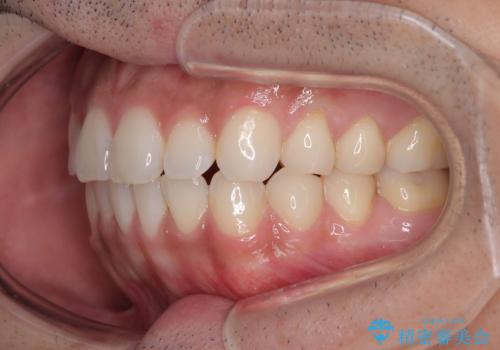

目立たない装置でデコボコを改善 ハーフリンガルによる矯正治療

- 上下顎歯列のデコボコを改善したいとのことで来院された患者様です。

自己管理の大変なインビザラインや、目立つ表側のワイヤー矯正は避けたいとのことで、

上顎だけ裏側装置のハーフリンガルにて矯正しました。

一年と数か月で矯正を終えることができました。